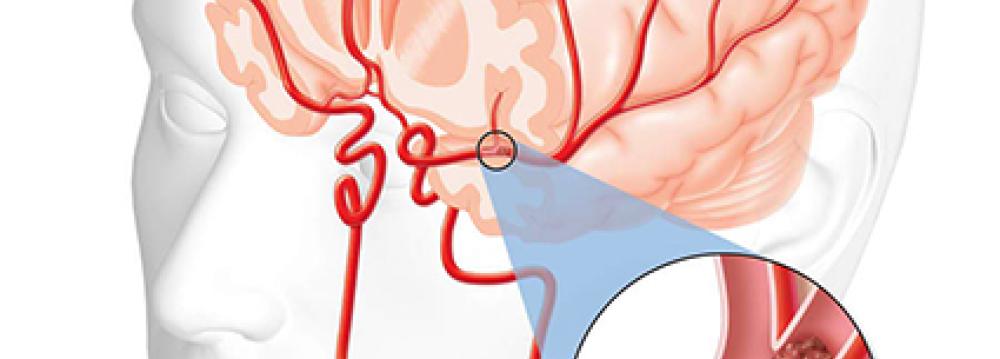

Contrary to public opinion, brain stroke is one of the most treatable human ailments, said Babak Zamani, head of Iranian Brain Stroke Association.

However, the most important hours for treatment of the health complication is within the first 2-3 hours after the onset of symptoms, and therefore the existence of well-equipped ambulances and constant presence of physicians in hospitals, helps lower the mortality rate of brain stroke, IRNA quoted him as saying.

Annually, nearly 160,000 people suffer from different types of strokes in Iran. “With the launching of the National Committee for Brain Stroke Treatment by the Health Ministry in mid 2016, the quality of services provided to the patients has improved significantly,” he added.